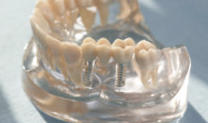

Implantologie

Die Implantologie eröffnet neue Wege und Möglichkeiten für die Zahnmedizin: Zahnverlust kann rückgängig gemacht werden.

Zahnersatz (digital)

Planung, Vorbereitung, Qualität der Ausführung und die zahntechnische Umsetzung sind entscheidend für hochwertige Ergebnisse.